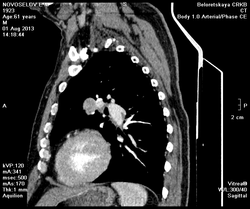

Мужчина оперирован по поводу BL щитовидной железы.Неоднократно проходил КТ в других лечебных учреждениях, у нас- впервые.Ставились заключения:MTS в лёгкие и лимф.узлы средостения слева.Образование слева увеличилось.Жалуется на одышку, не верит в заключение о MTS,просит узнать мнение других специалистов.

Метастазов в легкие не вижу. Похоже на лимфоузел в головке левого корня. Если позволите, запаздываете с началом исследования, плотность контраста в легочных артериях должна быть выше, чем а аорте. А одышка, не мудрено, легочная ткань диффузно уплотнена по типу "матового стекла", написал бы какую-нибудь интестициальную пневмонию, по типу альвеолита, может быть и гиперчуствительный пневмонит (не разберу есть или нет внутридольковые очажки), посмотреть бы изначально легочное окно, а не восстановленное из мягкотканного.

Коллега, вынужден извинться и дезавуировать свой первый пост. Пересмотрел. Да, есть очаги, и они - вероятнее всего, метастазы.

Единственное,что напрягает,так это то,что эти изменения у пациента более 1,5 лет.А вид внешний у него не так уж и плох.А слева это всё-таки лимфоузел, а не периферическое образование в S3?

Думаю, да. Слишком близко лежит к легочной артерии.